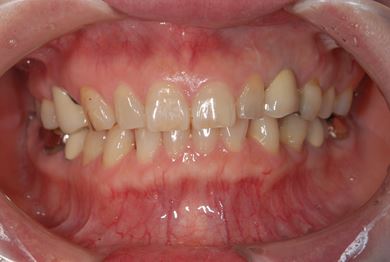

インプラントの症例写真 IMPLANT

インプラント治療

| 性別/年齢 | / 49歳 | ||||||||||||||||||||||||||||||||

| 主訴 | 乳歯がぐらついている。 | ||||||||||||||||||||||||||||||||

| 治療方針 | インプラント治療にて、機能的・審美的回復を行う。 | ||||||||||||||||||||||||||||||||

| 治療内容 | インプラント1本、メタルボンドセラミッククラウン1本 | ||||||||||||||||||||||||||||||||

| 総治療費 | 377,055円 | ||||||||||||||||||||||||||||||||

| 治療期間 | 4ヶ月 |